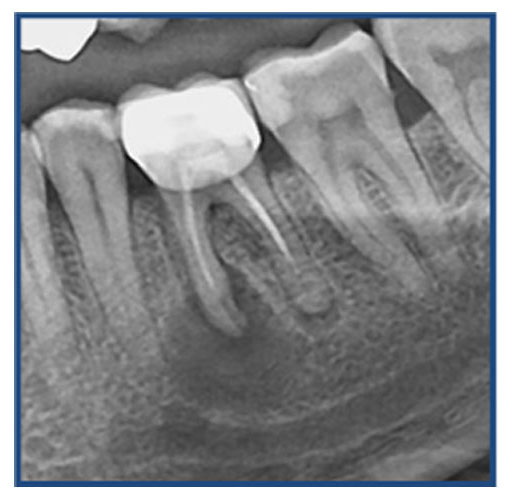

Ατελής ενδοδοντική θεραπεία που οδήγησε σε περιακρορριζική καταστροφή.

Η επανάληψη της ενδοδοντικής θεραπείας δεν οδήγησε σε πλήρη επούλωση της βλάβης,

καθώς είναι αναγκαία και η περιοδοντική θεραπεία του δοντιού.